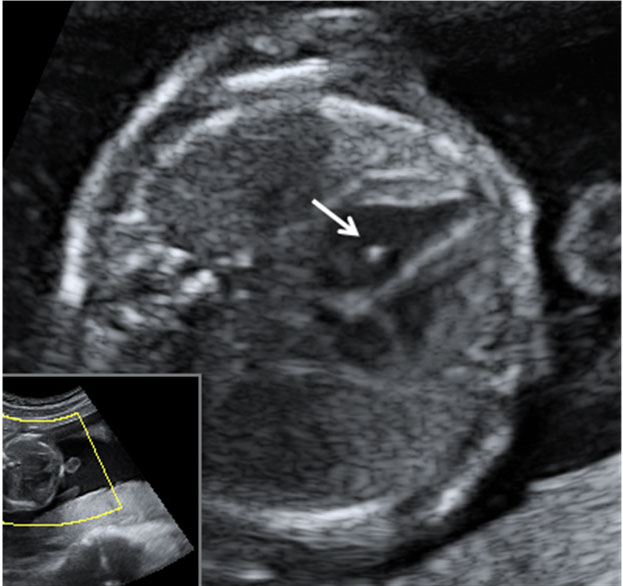

Corazón fetal en el que se aprecia una mancha brillante o foco ecogénito

La imagen de la flecha indica el foco ecogénito en el ventrículo izquierdo.

Ecografía Embarazo 2D y 3D Semana 20 - MALFORMACIONES FETALES